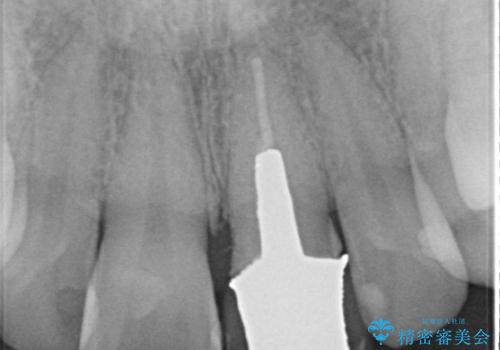

- 左上の前歯の形や色が気になる。

保険の前歯の被せ物のやりかえを希望して来院

- 28.6万円(内訳:根管治療11万円、土台2.2万円、仮歯1.1万円、オールセラミック[スペシャル]14.3万円)費用は治療当時の料金となります